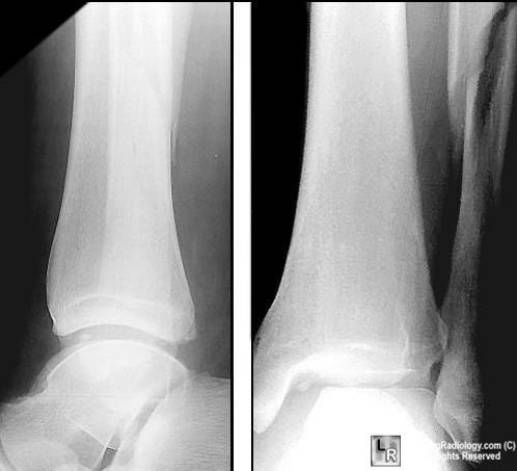

Pilon骨折

是指胫骨远端关节内骨折,常常由垂直暴力所致,常常合并腓骨骨折和严重的软组织损伤。

Dupuytren骨折

踝部旋转骨折伴下胫腓韧带断裂,包括下胫腓分离和腓骨下端骨折。